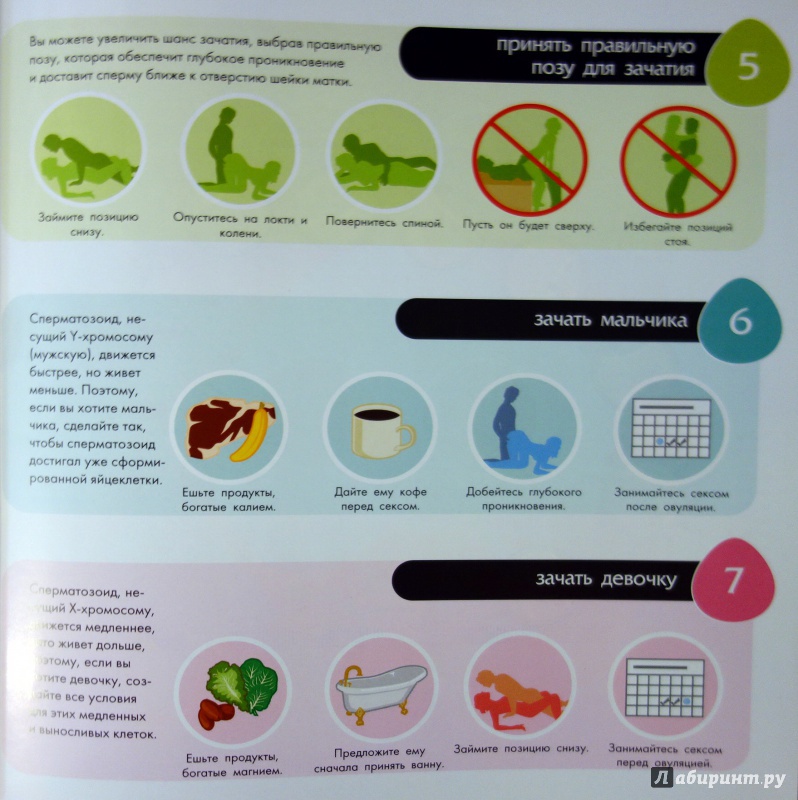

Рекомендации по зачатии